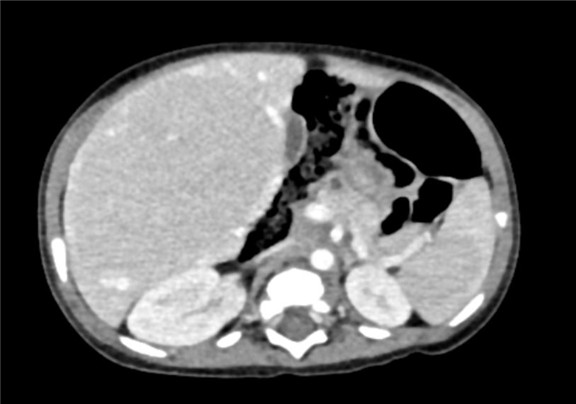

术前CT检查:

静脉期

下腹部增强CT示:肝内巨大占位,考虑肝母细胞瘤可能性大,建议MRI平扫+增强进一步检查,腹腔、腹膜后多发肿大淋巴结影,考虑转移瘤可能性大,肝内多发结节,考虑血管瘤可能性大,建议随访